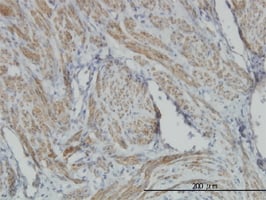

FOLR1, Polyclonal Antibody (Cat# AAA23491)